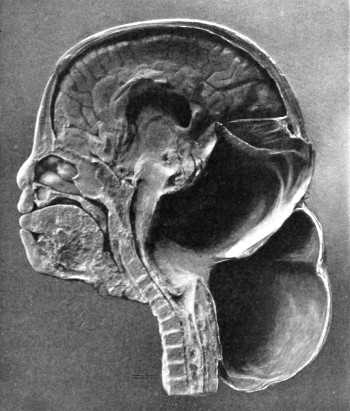

25. To illustrate the effects and position of a birth-hæmorrhage 53

26. The author’s operation for Hydrocephalus internus 64

27. The conversion of Hydrocephalus internus into cephalocele 65

28. Illustrating the lines along which forces received on the vault are transmitted to the base 69